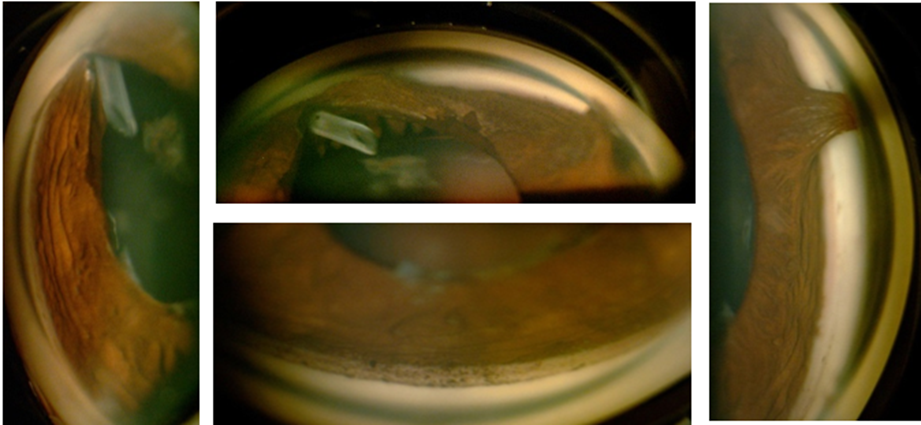

Figura 6-6. Gonioscopia: imagen real de ojo derecho, presencia de tubo valvular y sinequias anteriores periféricas.